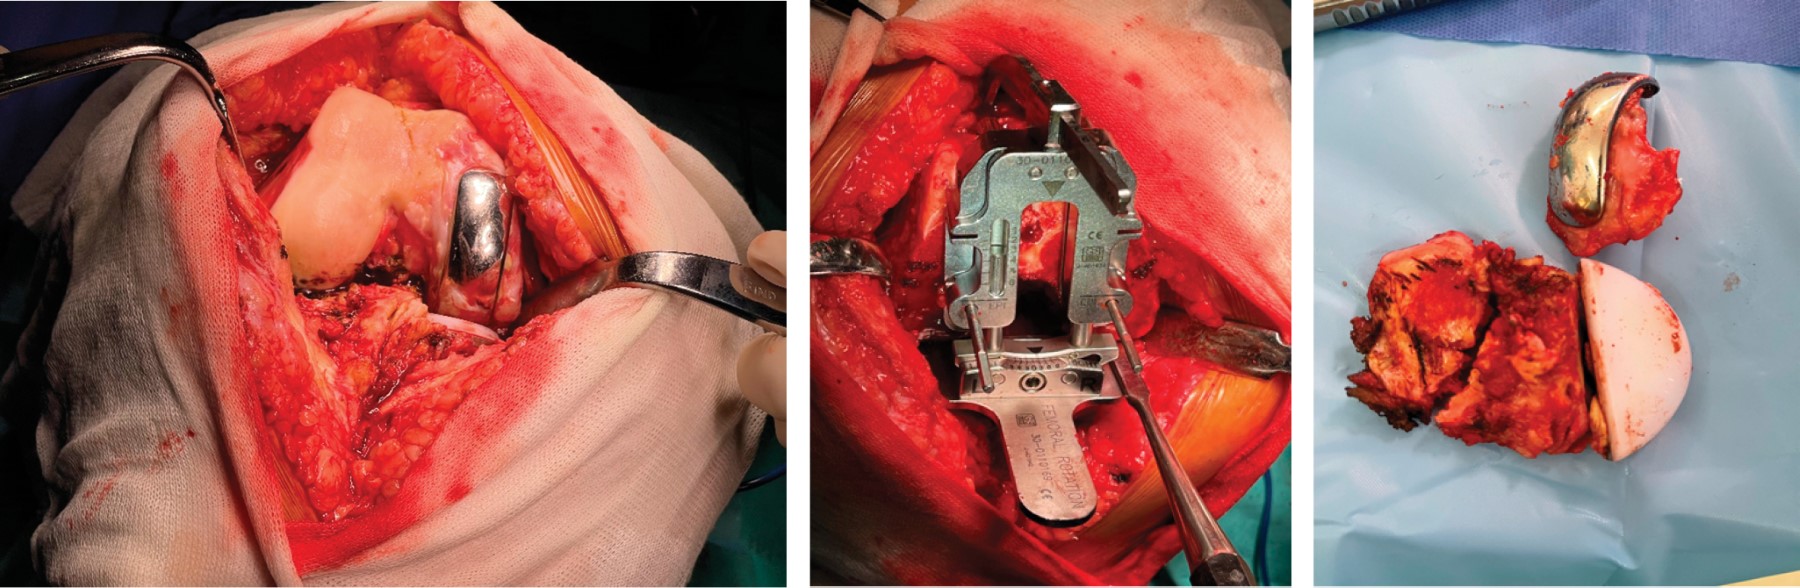

Figure 1

Figure 2

Figure 3